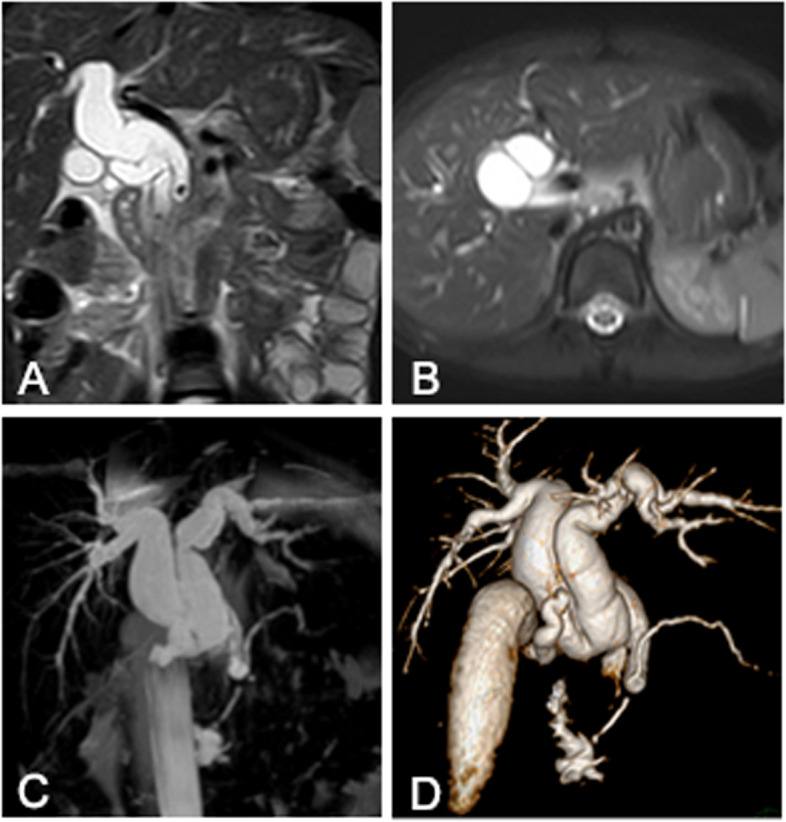

The patient is a 5-year-old Asian girl who had history of repeated abdominal pain for 4 days and aggravated for 1 day. Abdominal ultrasonography suggested dilatation of common bile duct with cholangitis, cholecystitis and abdominal effusion. Magnetic resonance cholangiopancreatography (MRCP) showed a common bile duct diaphragm which meant common bile duct duplication, with congenital biliary dilatation and cholelithiasis (Fig. 1). Symptomatic treatment including fasting, anti-infection, spasmolysis, and fluid rehydration was given. The temperature of the child was stable, and there were no obvious contraindications for surgery before operation. The patient underwent cholecystectomy and biliary tract plasty and Roux-en-y common bile duct jejunostomy and abdominal cavity irrigation and drainage under general anesthesia. Intraoperative cholangiography showed both distal openings into the duodenum and converged with the pancreatic duct (Fig. 2 A). The dilated sac wall of the common bile duct was partially removed, and the septum between the left and right hepatic ducts was excised and sutured to form a regular common bile duct. Intraoperative cholangiography(IOC) after repair showed that the morphology and drainage of common bile duct was normal, and large amounts of contrast medium entered the duodenum and jejunum(Fig. 2 B).The postoperative recovery of the child was good. Preoperative MRCP and IOC were shown in Figs. 1 and 2.